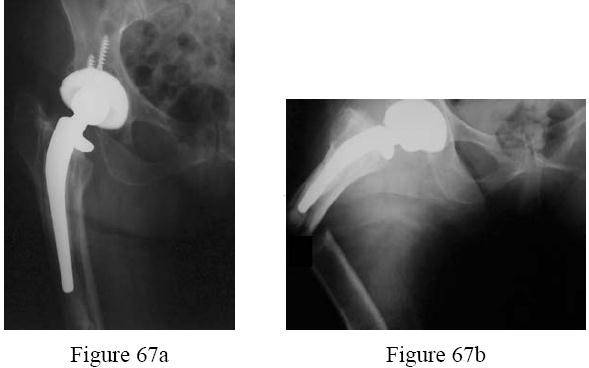

a is the radiograph of a 78-year-old woman who has a recent history of increasing thigh pain 12 years after undergoing total hip arthroplasty. Figure 67b is the radiograph after she fell and was unable to ambulate. What is the most appropriate treatment?

---

Explanation